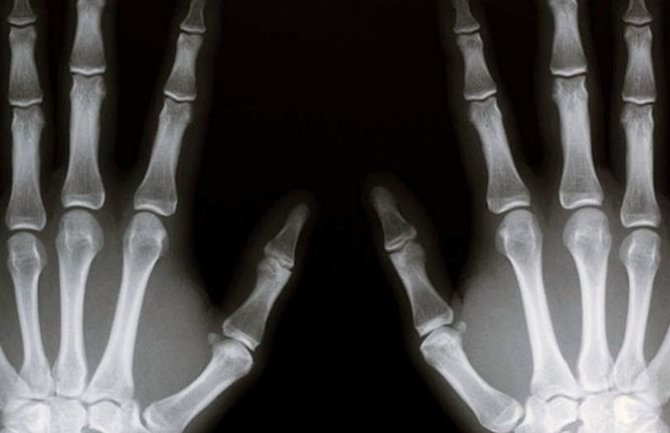

Snimci sredovječne Škotlanđanke pokazali su da su uvećani krvni sudovi vremenom zamijenili njeno koštano tkivo.

Pacijentkinja se ljekarima obratila zbog neprestanog bola u ramenu, a kada su putem rendgena otkrivene lezije u ramenoj kosti, ljekari su pomislili da je riječ o tumoru.

Nakon što se pacijentkinja nakon 18 mjeseci ponovo podvrgla rendgenskom snimanju, ljekari su primijetili da koštano tkivo u njenoj ruci i ramenu nestaje.